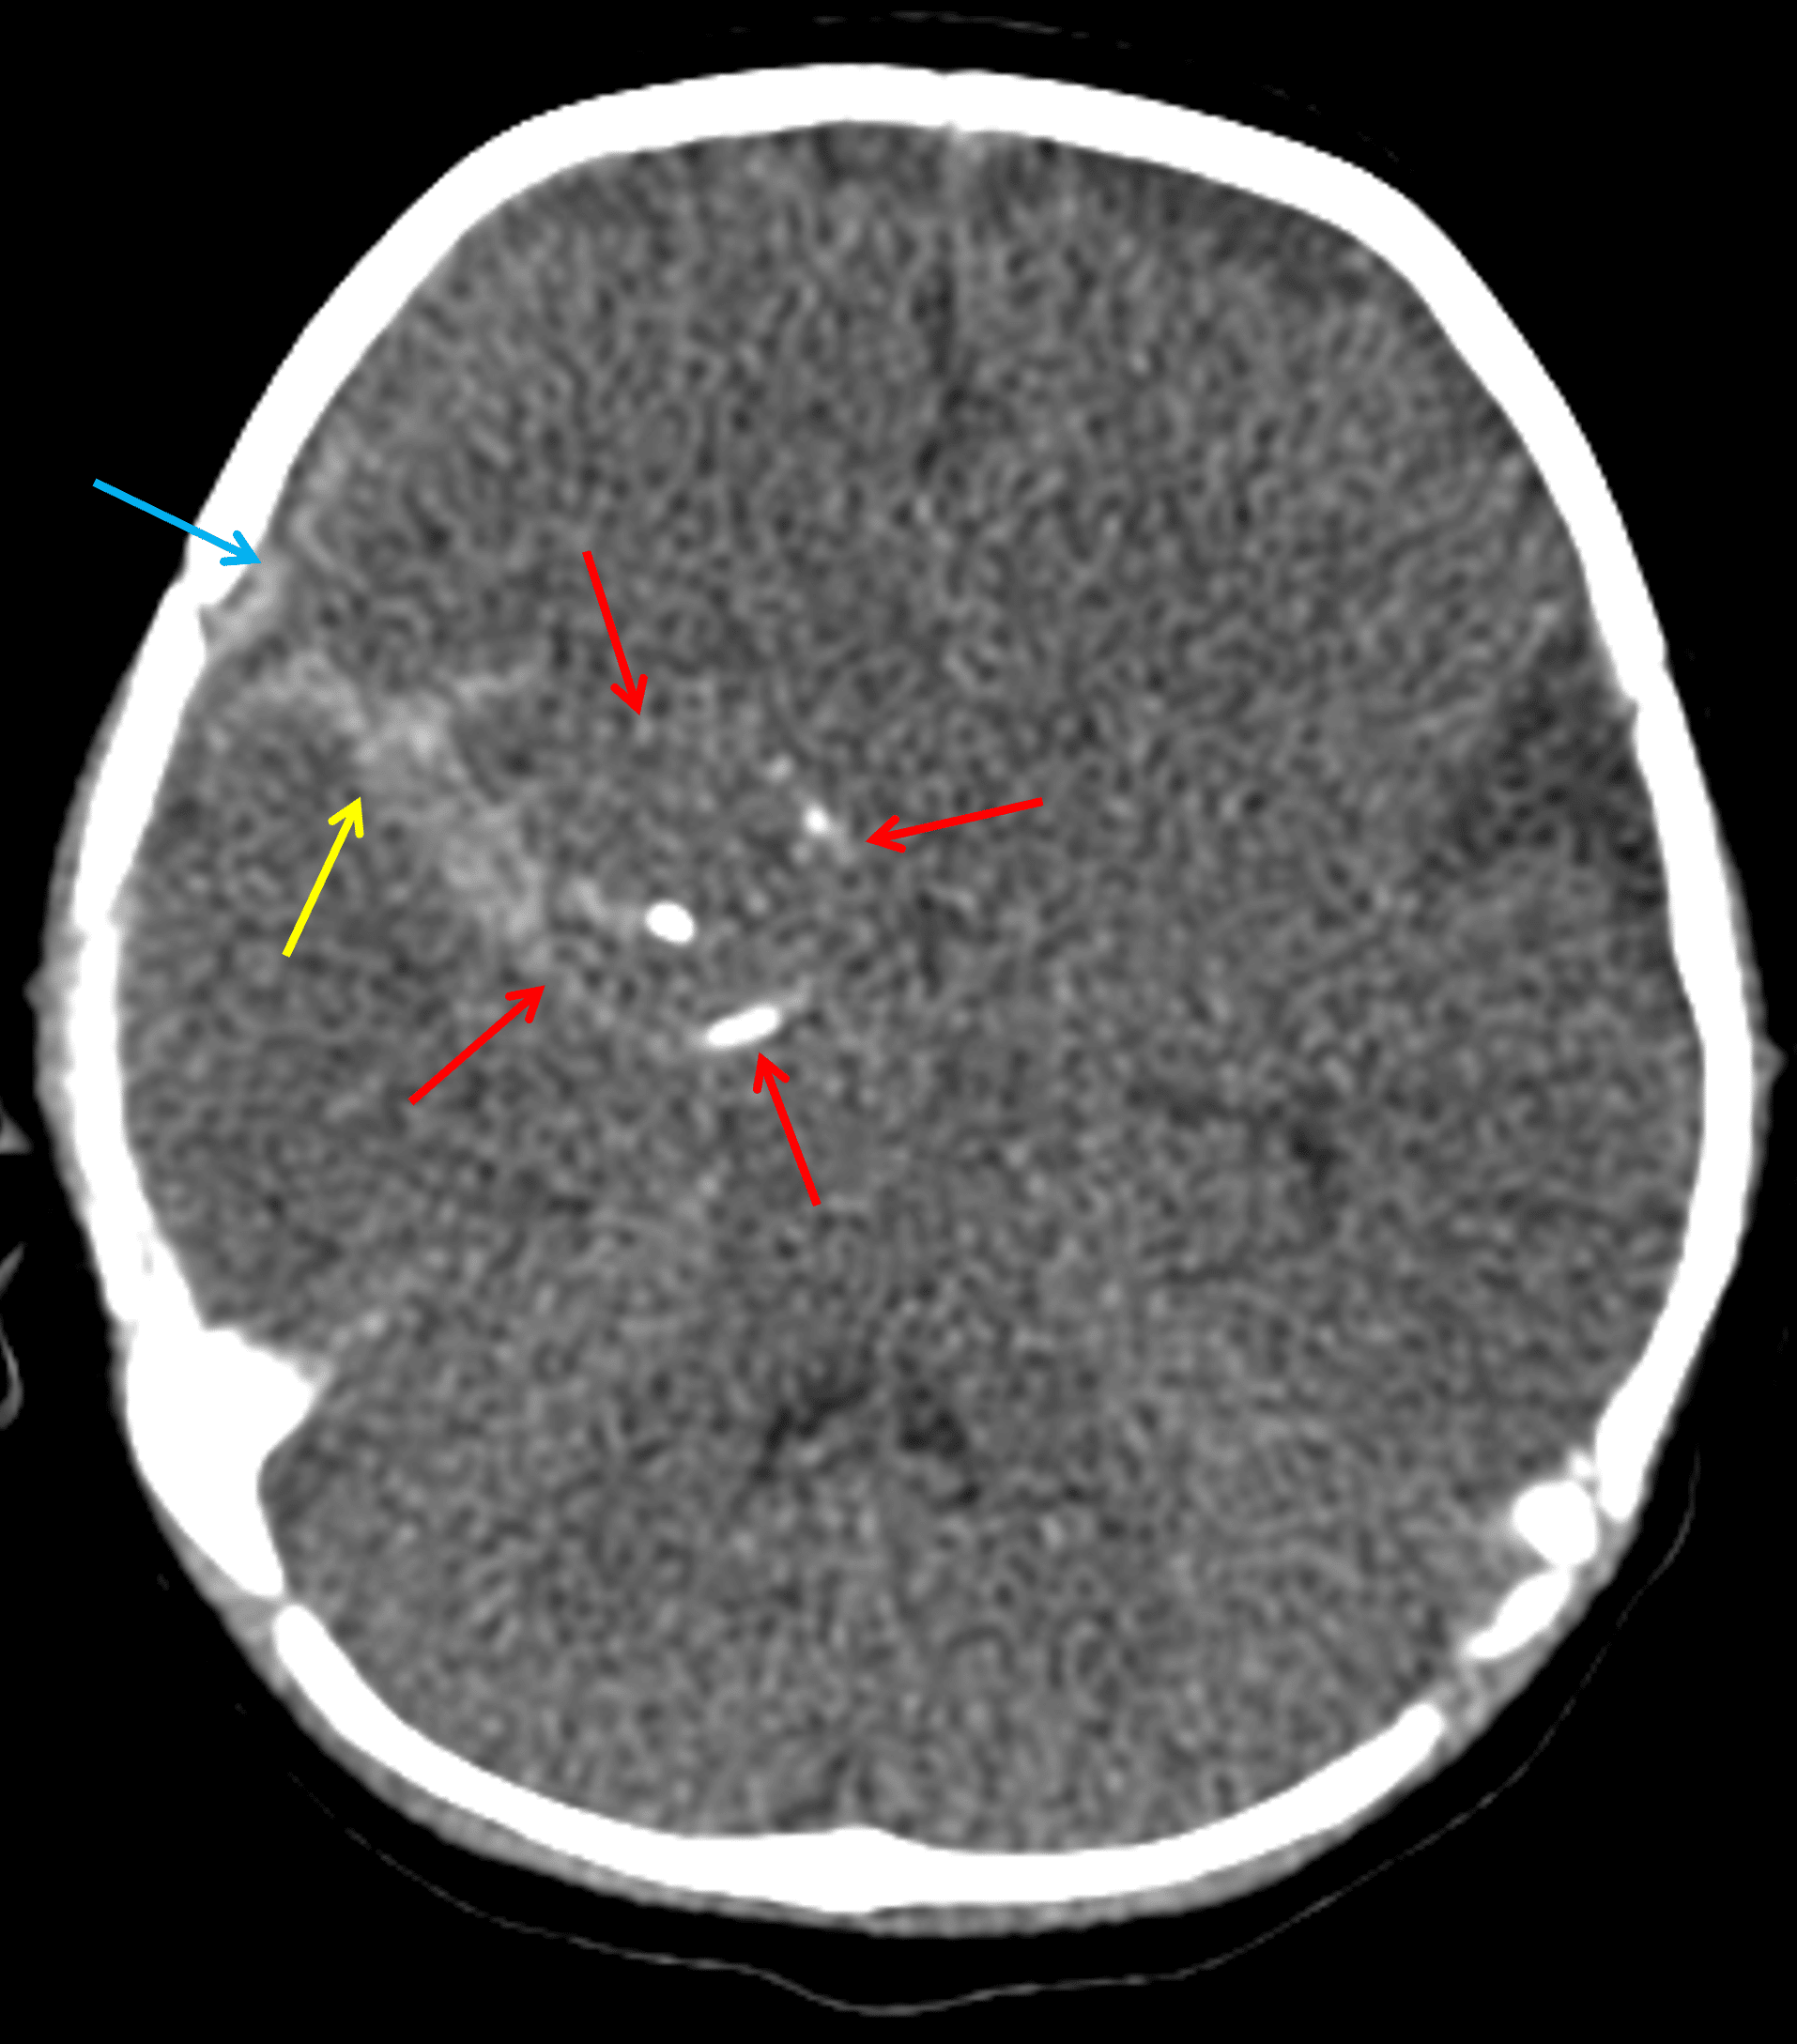

CT

- Peripherally-calcified mass along the medial right temporal lobe with adjacent small volume subarachnoid and subdural hemorrhage tracking along the floor of the right middle cranial fossa

Peripherally-calcified lesion along the right temporal lobe (red arrows) with adjacent subarachnoid (yellow arrow) and subdural (blue arrow) hemorrhage.